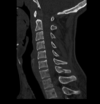

Fratura do processo odontoide

Tipo III de Anderson e D’alonzo.

Envolve o corpo de C2.

Estável, melhor prognóstico;